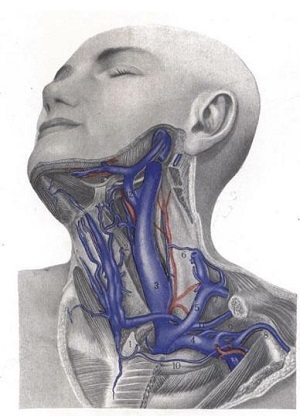

Анатомия внутренней яремной вены: КТ изображения